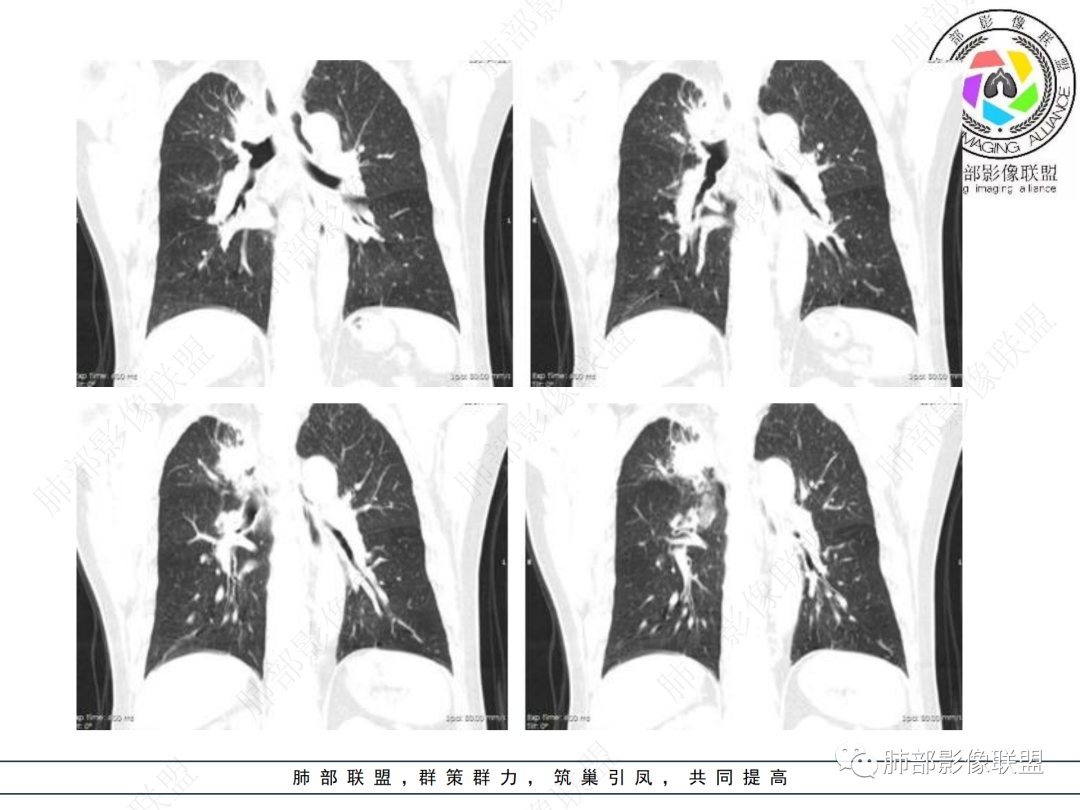

右肺上叶可见一团块影,边界清,有膨隆有凹陷,边缘可见毛刺,斜裂可见牵拉,不均匀强化,内可见液化,临近支气管未见明确阻塞,考虑腺癌可能,鉴别脓肿,结核等

右肺上叶团块,边缘毛糙,长索条,周围斑点影,邻近胸膜增厚,不均匀强化,其内小低密度灶边界清,考虑炎性肉芽肿,腺癌待排

右上胸廓缩小,叶间裂移位,尖段软组织影,前段支气管壁增厚,双上肺多发结节及条片影,增强后尖段软组织影内见多发低密度影,呈环状强化,考虑慢性肉芽肿,腺癌待排

男性,69岁 反复咳嗽2年余,加重3天入院。CT示右肺上叶尖段不规则实变影,周边伴条索影,支气管未见明显堵塞,增强不均匀强化,考虑为恶性,腺癌可能

老年男性,慢性病程,右肺上叶团块影,边界清晰,边缘毛刺,脐凹征,胸膜牵拉,不均匀强化,支气管壁增厚,考虑恶性,腺癌可能,鉴别肉芽肿、结核

男,69,反复咳嗽2年,加重3天入院,右肺上叶软组织密度肿块影,边界尚清晰,边缘见毛刺及胸膜牵拉,右肺上叶支气管壁增厚,增强扫描不均匀性强化,考虑腺癌可能,鉴别炎性病变。

老年男性,右肺上叶体积小,见高密度团块,边缘模糊,并见多发长索条,增强后不均匀强化,考虑炎性肉芽肿性病变,鉴别腺癌

病程长,右肺上叶团片影,边缘毛糙,部分膨隆,长索条,周围长条索及结节,邻近胸膜增厚,不均匀强化,首先考虑炎性肉芽肿,鉴别腺癌

右肺上叶团块周围多发斑索,不均匀强化,支气管无明显堵塞,咳嗽两年,首先考虑慢性炎性病变,肺结核可能,鉴别腺癌

右肺上叶见不规则团块,边缘清晰,周围可见长索条及斑片影,胸膜顶增厚,右侧斜裂部分增厚,右上肺体积略缩小,增强后不均匀强化,考虑炎性肉芽肿性病变,结核?鉴别腺癌

右肺上叶体积变小,见不规则实性病灶,边缘有平直,长软毛刺,邻近胸膜明显增厚,叶间胸膜牵拉上提、局部凹陷;病灶周围不干净,可见长索条影;近端支气管壁略增厚。增强后增强不均匀,有低密度坏死,间隔较厚。考虑慢性炎性肉芽肿,结核可能,鉴别腺癌。

右侧胸廓变小,右肺上叶团块,边缘毛糙,长索条,周围斑点影,邻近胸膜增厚,气管不规整,密度不均,不均匀强化,考虑炎性肉芽肿,腺癌待排。